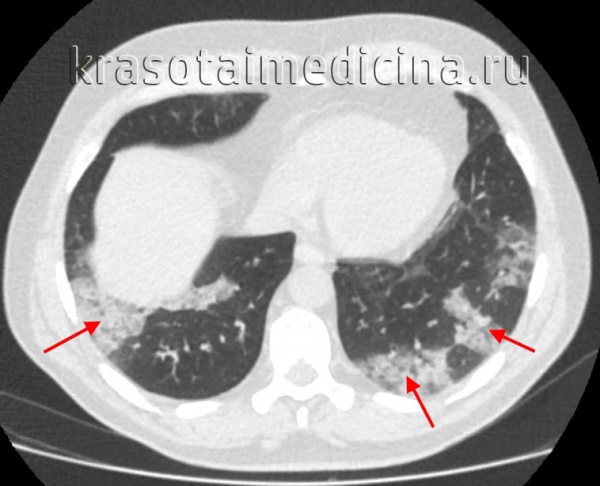

КТ ОГК. Множественные обширные участки снижения пневматизации по типу консолидации в нижних долях обоих легких.

3. КТ легких при бактериальной пневмонии:

• Консолидация (например, при поражении дыхательных путей):

о Сегментарные или субсегментарные участки консолидации

о Разбросанные «пятнистые» участки консолидации, часто с перибронховаскулярным распределением (бронхопневмония)

• Кавитация и пневматоцеле (золотистый стафилококк), абсцесс и гангрена легкого (Klebsiella pneumoniae)